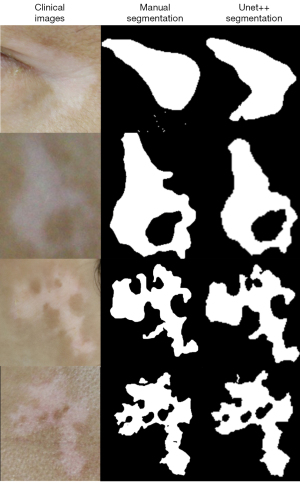

In a test set of 167 lesions and 100 controls, the YOLO v3 architecture correctly identified 155 lesions (sensitivity 92.91%), with an overall error rate of 14.98% (40/267). Twenty-eight cases (10.41%) were wrongly labeled. Among these, 16 cases of light reflections and 6 cases of light-pigmented facial parts were misclassified as vitiligo lesions. In addition, the architecture failed to detect 12 cases (7.19%) of vitiligo lesions, most of which were either small in size (6/12, 50%) or located on the scalp or near the mouth (3/12, 25%). For the segmentation of vitiligo lesions, the UNet++ architecture showed the best performance, with a JI of 0.79 in comparison with the PSPNet (JI: 0.746) and UNet (JI: 0.706) architectures (P<0.05; Figure 3). Consequently, UNet++ was integrated into the model. On the additional test set, however, the model achieved a lower detection sensitivity of 72.41% (105/145), as well as a lower segmentation JI of 0.69.

Lesion segmentation, namely separating lesions from surrounding normal skin, is a critical step in the evaluation of skin diseases. Although several segmentation methods for vitiligo have been reported (32,40-42), the DCNN-based approach is scarce in the literature. In the present study, we trained and validated the UNet++ architecture, which is a powerful DCNN for diverse medical image segmentation tasks. It achieved a JI of 0.79, which was better than that of UNet and PSPNet when compared with dermatologists’ manual segmentation. Recently, Low et al. reported a modified UNet architecture that used a ResNet50 contracting path for the segmentation of vitiligo lesions (43). Although trained on a small sample set, it scored 0.815, a higher JI than that of our model. It also showed a superior segmentation to the original UNet, especially on lesions of complex morphology. Our future work may thus explore and fuse together modalities with the best performance from different DCNNs to enhance the segmentation capacity of the AI model.